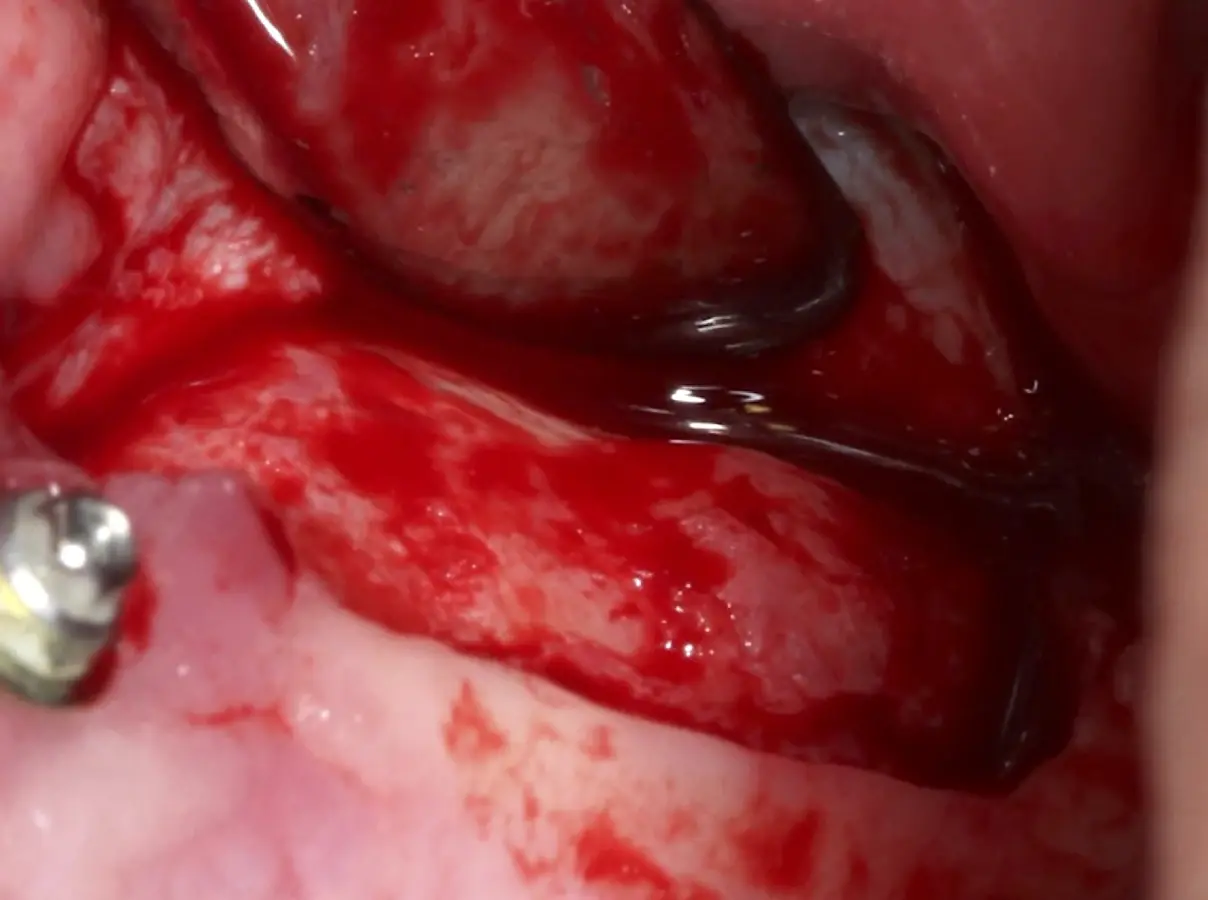

La técnica se inicia con la colocación de anestesia infiltrativa, posteriormente se realiza una incisión crestal o paracrestal con posibles liberantes verticales que deben de estar alejadas por lo menos 5 mm de los límites de la futura ventana y sobrepasar la línea mucogingival. Se realiza una elevación de colgajo, se inicia la antrostomía y antroplastía. Para ello, se emplea el inserto redondo diamantado de corte al momento de delimitar los bordes de la ventana de acceso. Luego se cambia al inserto aserrado liso de calibre fino con superficie diamantada, para profundizar y eliminar el hueso en el contorno de la ventana. Una vez que se traslucen los tejidos, se puede optar por el retiro de la tapa ósea o el levantamiento de ésta junto con la membrana.

Se inicia la elevación de la membrana de Schneider con el inserto redondeado no cortante en forma de disco, empleando movimientos suaves. El levantamiento puede complementarse con elevadores convencionales, siguiendo la dirección mesiodistal. La fase de desprendimiento inicia con el piso y sigue hacia la pared mesial para terminar, y de ser necesario, hacia la pared posterior. Existen diversos insertos con angulaciones y longitudes para mayor accesibilidad16 (Figura 1).

El clínico puede retirar la tabla ósea o introducirla como “tienda de campaña” dentro del seno maxilar. En cualquiera de las alternativas, es importante evaluar la presencia de tabiques óseos y de la arteria postero alveolar superior.